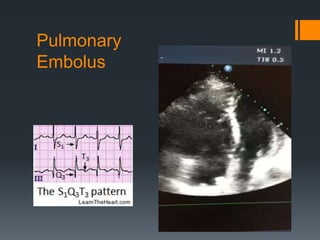

Pulmonary Embolus

Px: dyspnea, tachycardia, pleuritic cp, hypoxia,

hypotension

Etiology: surgery, cancer, immobilization, DVT,

indwelling catheter, pregnancy/OCP

S4, RV strain

S1Q3T3 (<7%), A-a gradient, hypoxia, Hampton’s

hump/Westermark sign

Dx: CT Angio, V/Q scan, D-dimer

Tx: Anticoagulation, thrombolysis

Pulmonary Embolus Px: dyspnea,tachycardia, pleuritic cp, hypoxia, hypotension Etiology: surgery, cancer, immobilization, DVT, indwelling catheter, pregnancy/OCP S4, RV strain S1Q3T3 (<7%), A-a gradient, hypoxia, Hampton’s hump/Westermark sign Dx: CT Angio, V/Q scan, D-dimer Tx: Anticoagulation, thrombolysis

• #19 TTE: underfilled LA and “D-sign” from large RV